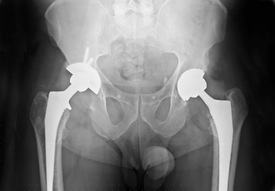

Hip replacement surgery involves the removal of the femur and hip joint. They are then replaced with artificial parts that are designed to allow for normal and healthy movement. Unfortunately, with older technology, these replacements often needed to be replaced themselves, leading to expensive and difficult repeat surgeries. The promise of the Zimmer Durom hip cup was that it would allow younger hip replacement recipients to use one replacement for the rest of their lives. Unfortunately, this has not been true.

Unfortunately, many of those patients who have been given the Zimmer Durom hip cup as a part of their hip replacement have needed to have further surgery. This is a surprise, because this particular device is marketed to younger hip replacement patients purposefully, so that they will not need further surgery. In fact, at one hospital which used the hip cup, 12 percent of those patients who received them needed further surgery within two years, a large number indeed. When contacted by the hospital, they were told that the issue was with ‘surgeon error,’ and not with the device.

The issue is not with surgeon error, but with the implant itself. When the Zimmer Durom hip cup was tested by the company, eight percent of those who received it needed a replacement in under two years. This number is incredibly high, and has led to serious problems for those needing a new replacement, and for those who are worried that their hip replacement may fail. Because of these issue, a class action law suit is being filed.